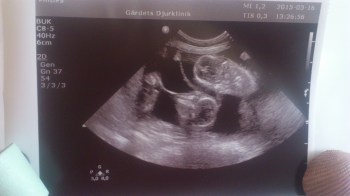

I måndags var Love och jag på ultraljudsundersökning. Fyra små hjärtan som tickade syntes – och vilken aktivitet det var där inne i den lilla rund magen.